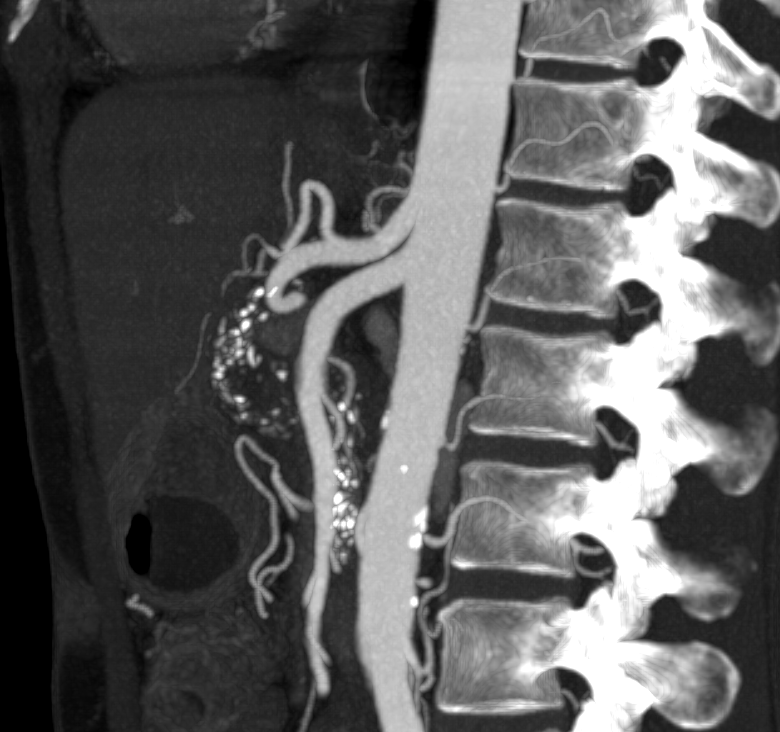

3. Lumbar arteries on angiography